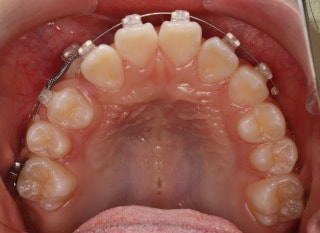

小児期第二段階

開始時

治療中